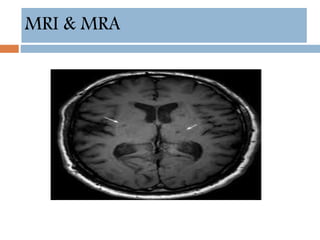

MRI & MRA